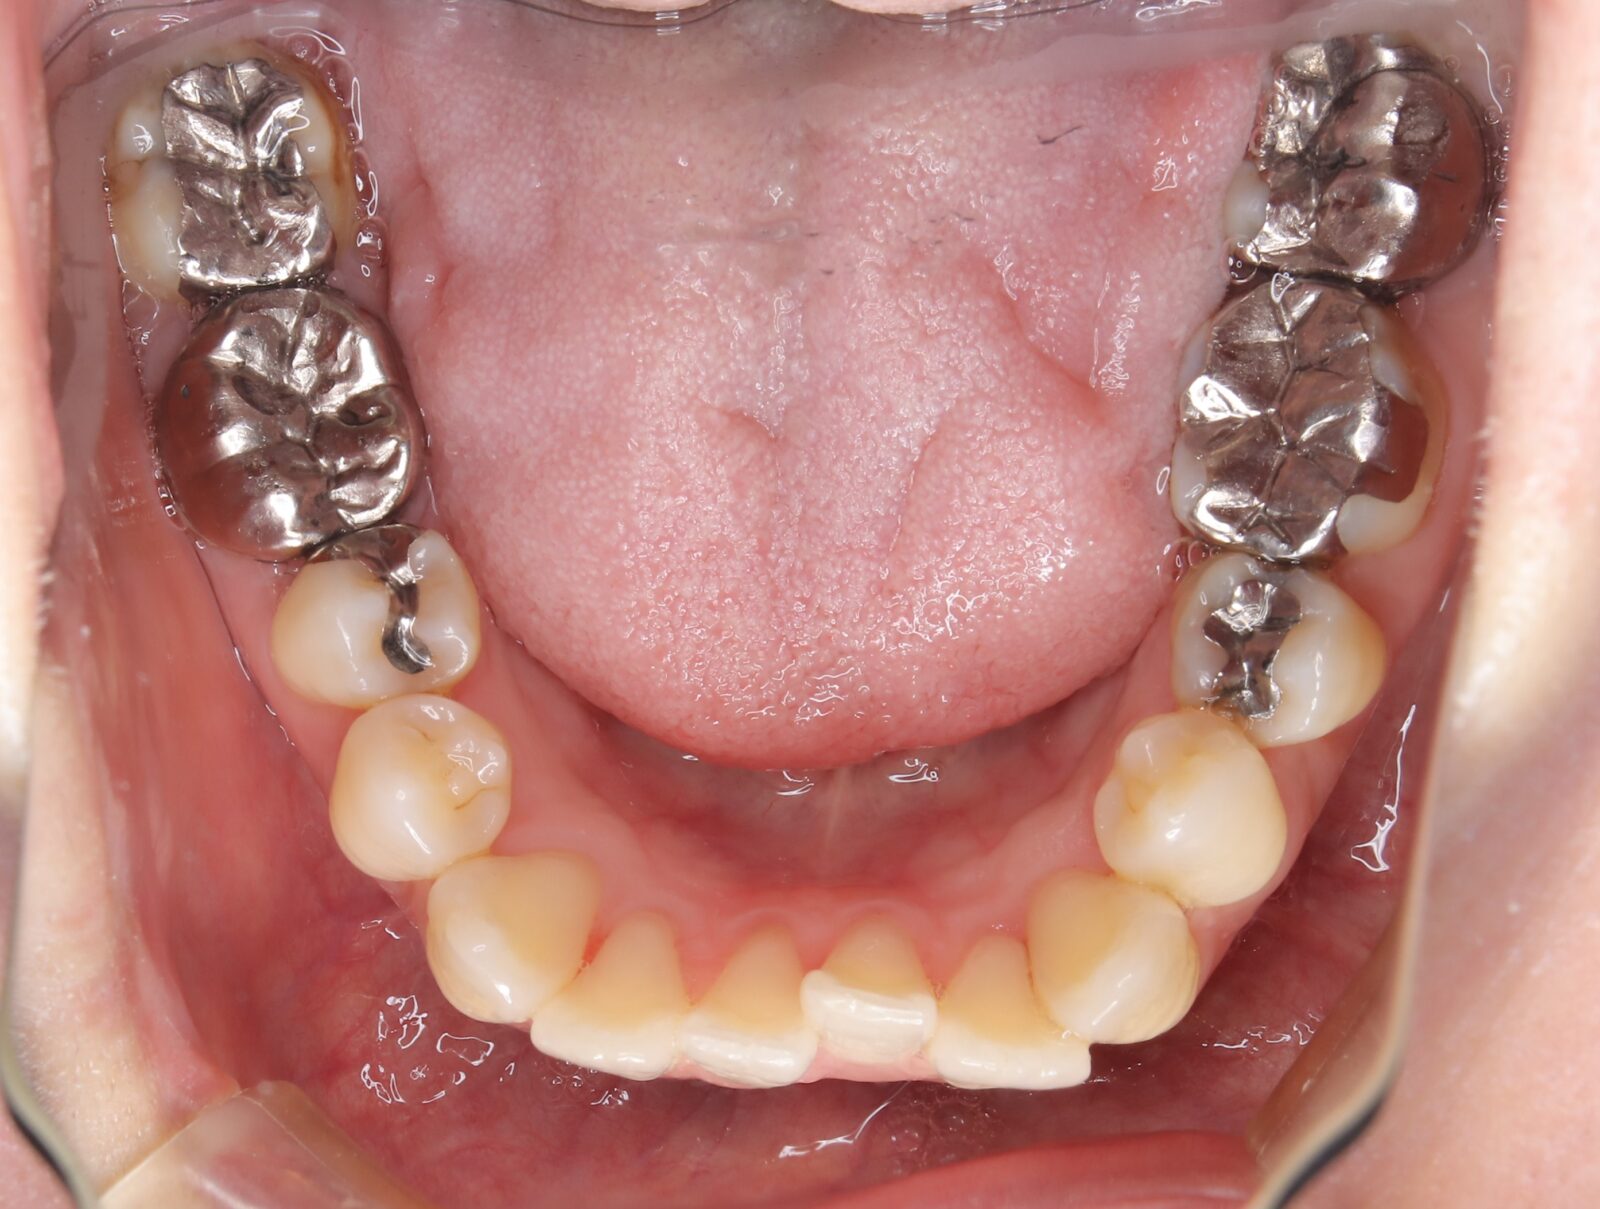

矯正と補綴が必要で実施した症例

左側に隙間。歯の数が少ない。もともと2番と7番がない。(先天欠如)歯の数が少ないため上顎のアーチ全体が小さい。歯槽骨の幅も狭く、歯肉も薄い。骨質も弱かった。

上顎左右2番と6番が先天欠如。下顎左右1番も先天欠如でもともとブリッジが装着されていた。

左右非対称なすきっ歯。上顎の前歯がないので左側の隙間を左右2番相当部に集めた。

上下の前歯が反対の噛み合わせ(受け口)で、干渉しているためうまく閉じることができず、奥歯は左右同時に噛めないので、どこかにずらさないと口を閉じられない。

左右の歯を同時に合わせることができず、どこで噛んだら良いかわからない噛み合わせでした。

小臼歯部は噛み合うことがない側方の開口状態。矯正と補綴が必要なケース。 主訴は顎の不調と歯軋り、夜間の食いしばり。

マルチブラケットとインビザラインを併用し、クラウンとブリッジを装着しました。

上顎左右2番は、歯が入るスペースを作り、ブリッジを装着しました。

他の歯医者で何軒も断られていました。 骨の幅がうすくインプラントはできない。骨の質も柔らかい。PCR検査の結果も歯周病ハイリスク患者でした。

歯の位置は、本人の顎が安定する場所を探して着地した。 左右で噛み合わせが非対称で、理想的な歯のポジションを獲得できなかったものの、左右同時に噛むことができるようになった。

顎関節の症状も落ち着いて、開口障害や、顎の痛みは無くなった。

矯正治療はどの装置を選択しても歯周病のリスクを高めてしまう。

これ以上の歯の移動が歯周病と骨質、骨の代謝のバランスの兼ね合いで困難であると判断し、ここが着地点とした。